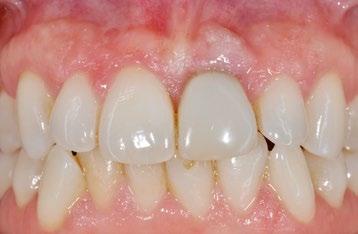

terior. En el plano vertical, se logró una buena corrección de la mordida profunda anterior gracias a la vestibularización de los incisivos, programada para resolver el apiñamiento. Esto se confirma con los valores cefalométricos obtenidos de la telerradiografía lateral realizada al final del tratamiento (Fig. 7). De hecho, tanto los incisivos superiores como inferiores experimentaron un aumento en su inclinación con respecto a las bases óseas respectivas de aproximadamente 4° (U1-pp: 109° e IMPA: 99°), permaneciendo dentro de un rango de normalidad. No se observaron cambios adicionales a nivel esquelético.

En la evaluación extraoral al final del tratamiento (Fig. 8), se observa una mejora en la estética de la sonrisa, con las líneas medias dentales correctamente alineadas con respecto a la línea media facial. Sin embargo, no se observaron cambios significativos en el perfil.